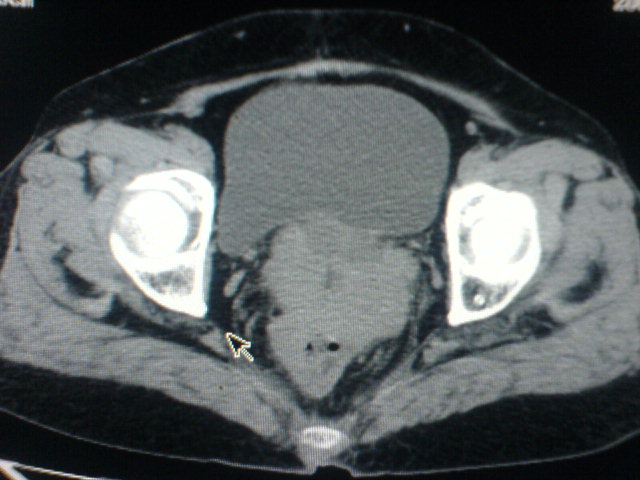

患者为老年女性,肿块最大层面不是位于宫颈,但宫颈偏后方有一囊状低密度影,肿块主要位于乙状结肠及直肠,所以考虑乙状结肠及直肠癌浸犯宫颈可能性大。

患者女性60岁 病史不详

宫颈癌侵犯直肠可能

考虑子宫内膜癌浸犯直肠。

考虑直肠癌侵及宫颈可能;建议增强扫描。

支持考虑宫颈癌上下前后通吃

考虑:直肠及乙状结肠癌侵及宫颈,囊性转移(假性粘液瘤)

支持宫颈癌侵犯直肠。

考虑直肠及乙状结肠癌侵犯邻近结构。